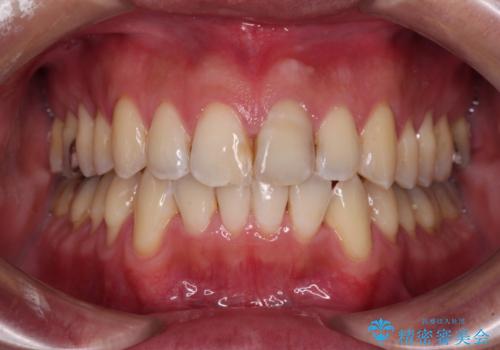

下顎にワイヤー装置を装着し、暫くしたところでやはりインビザラインにて矯正治療をしたいとのことで、インビザラインに切り替えました。

短い期間でしたがワイヤー装置を使用したことでデコボコが解消されたため、インビザラインの比較的短い期間で矯正治療を行うことができました。